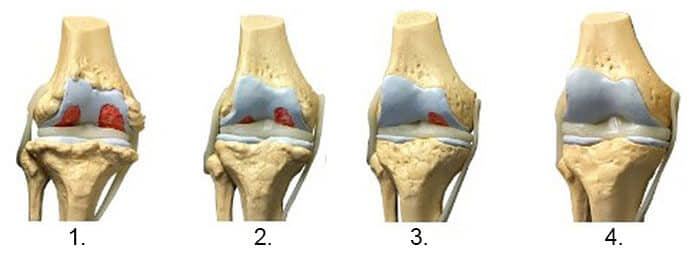

1. Недостаток на исхрана во зглобот. Ткивото на 'рскавицата се уништува.

2. Обновување на 'рскавичното ткиво на зглобот после 2 недели употреба на Arthro Blue.

3. Обновување на 'рскавичното ткиво на зглобот по 3 недели употреба на Arthro Blue.

4. Здрав зглоб по еден третман на лекување со Arthro Blue.